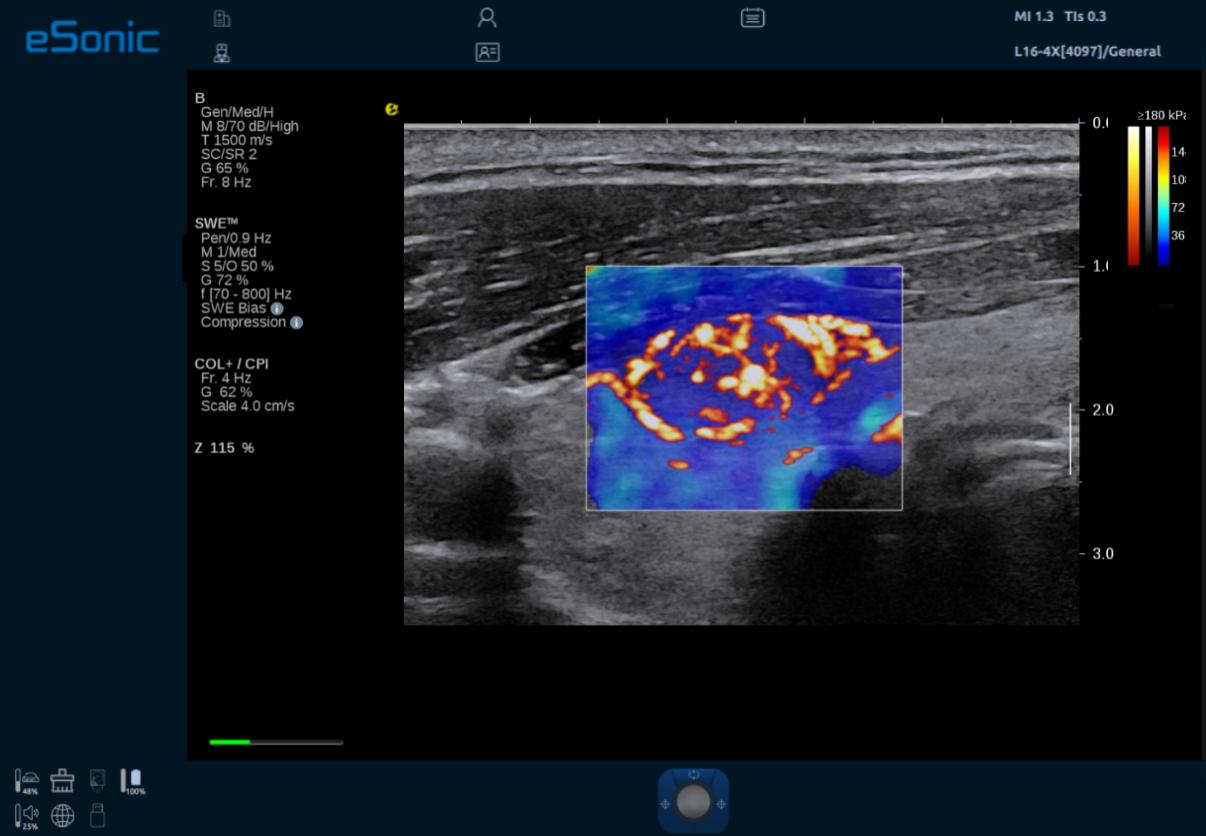

3D RTSWE 三维剪切波硬度定量成像

eTriplex 弹性三同步成像